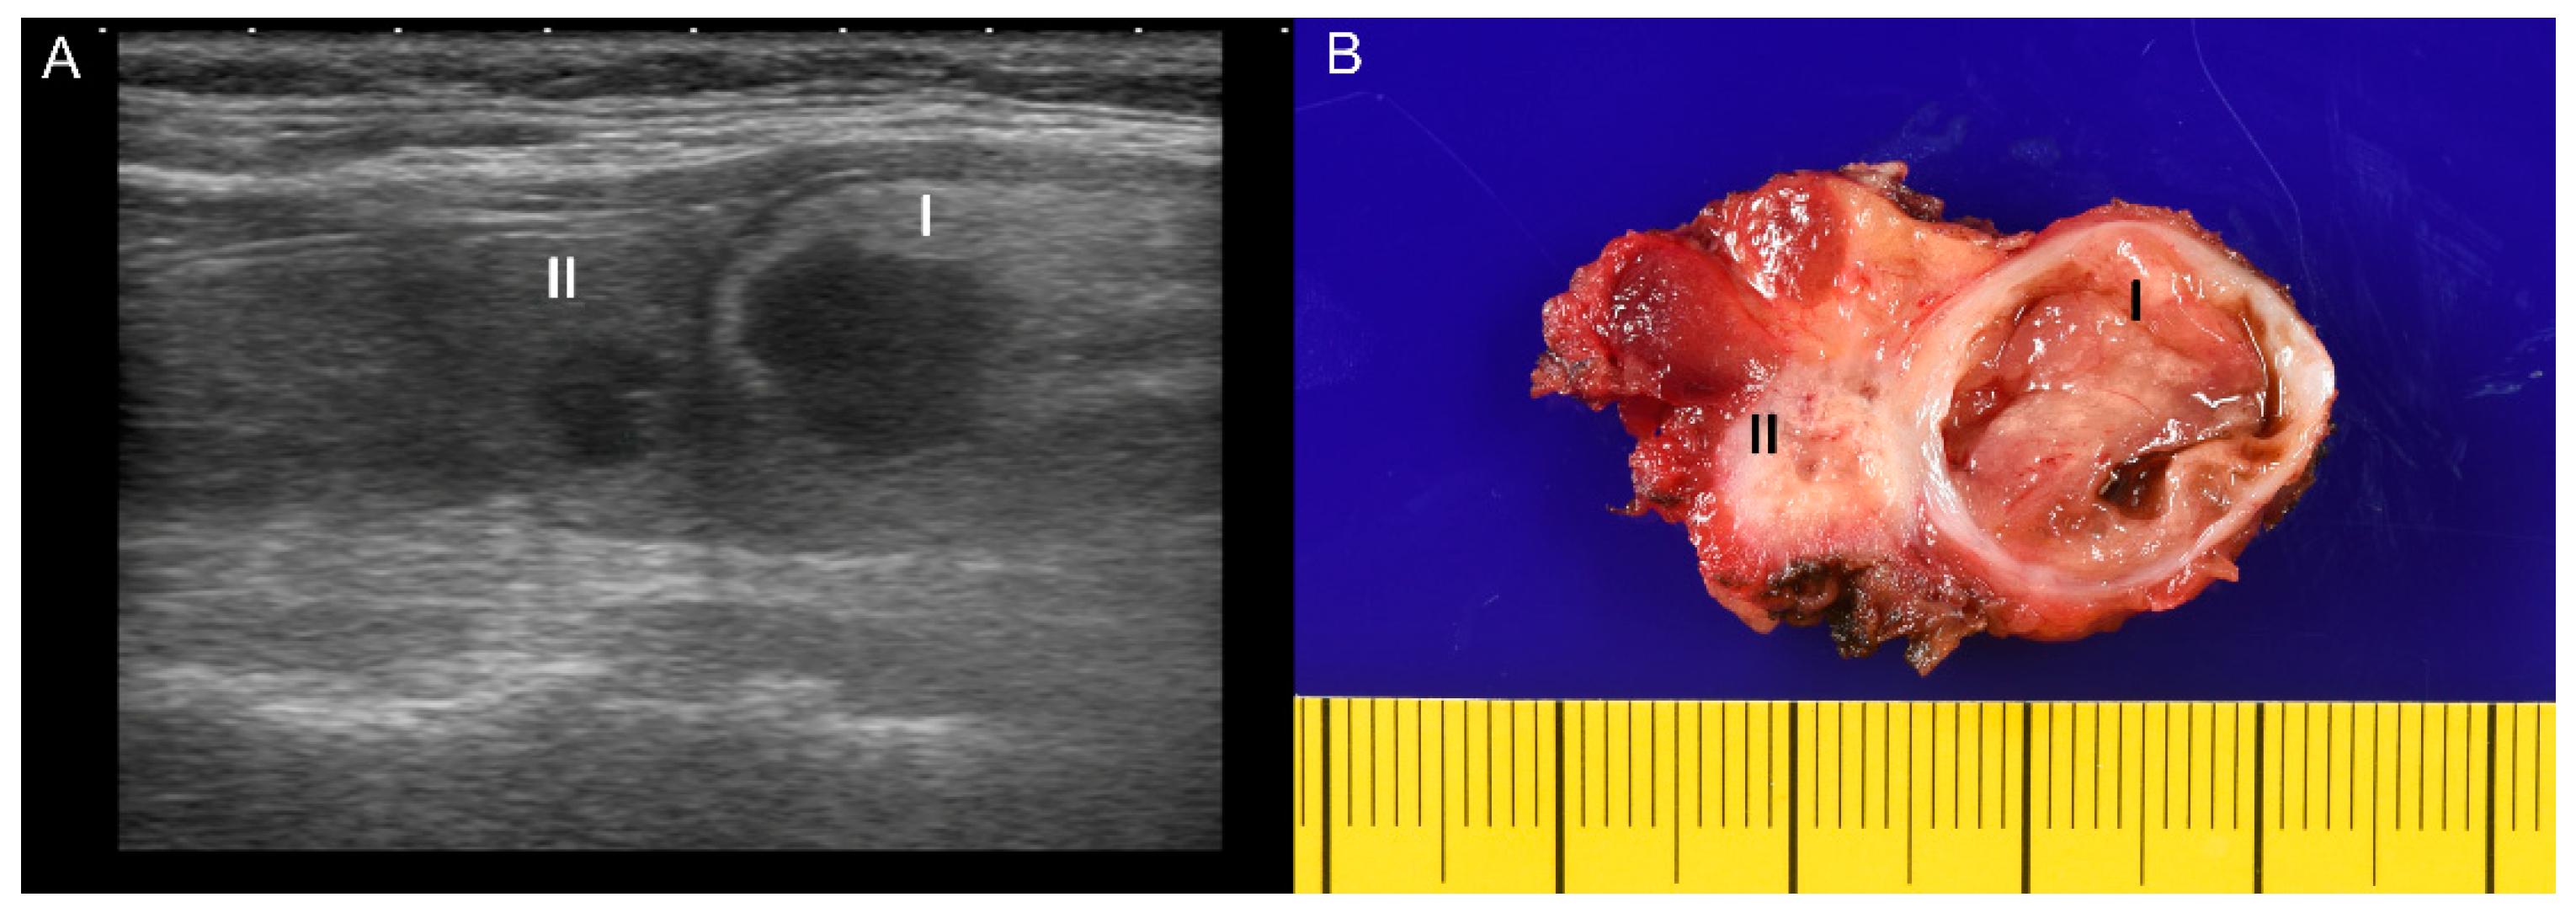

2. Case Presentation